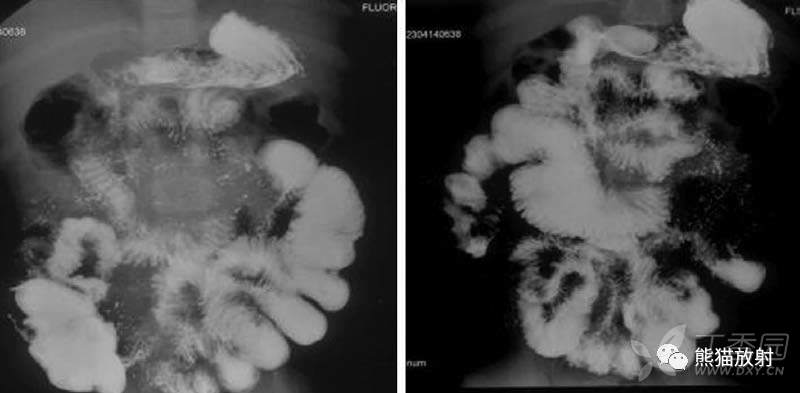

小肠钡剂通过迅速,部分小肠形态固定。

早期肠结核可见粘膜不规则和毛刺样改变。

多发性小肠狭窄伴部分扩张

小肠狭窄与扩张并存,形态固定,小肠粘膜增厚。